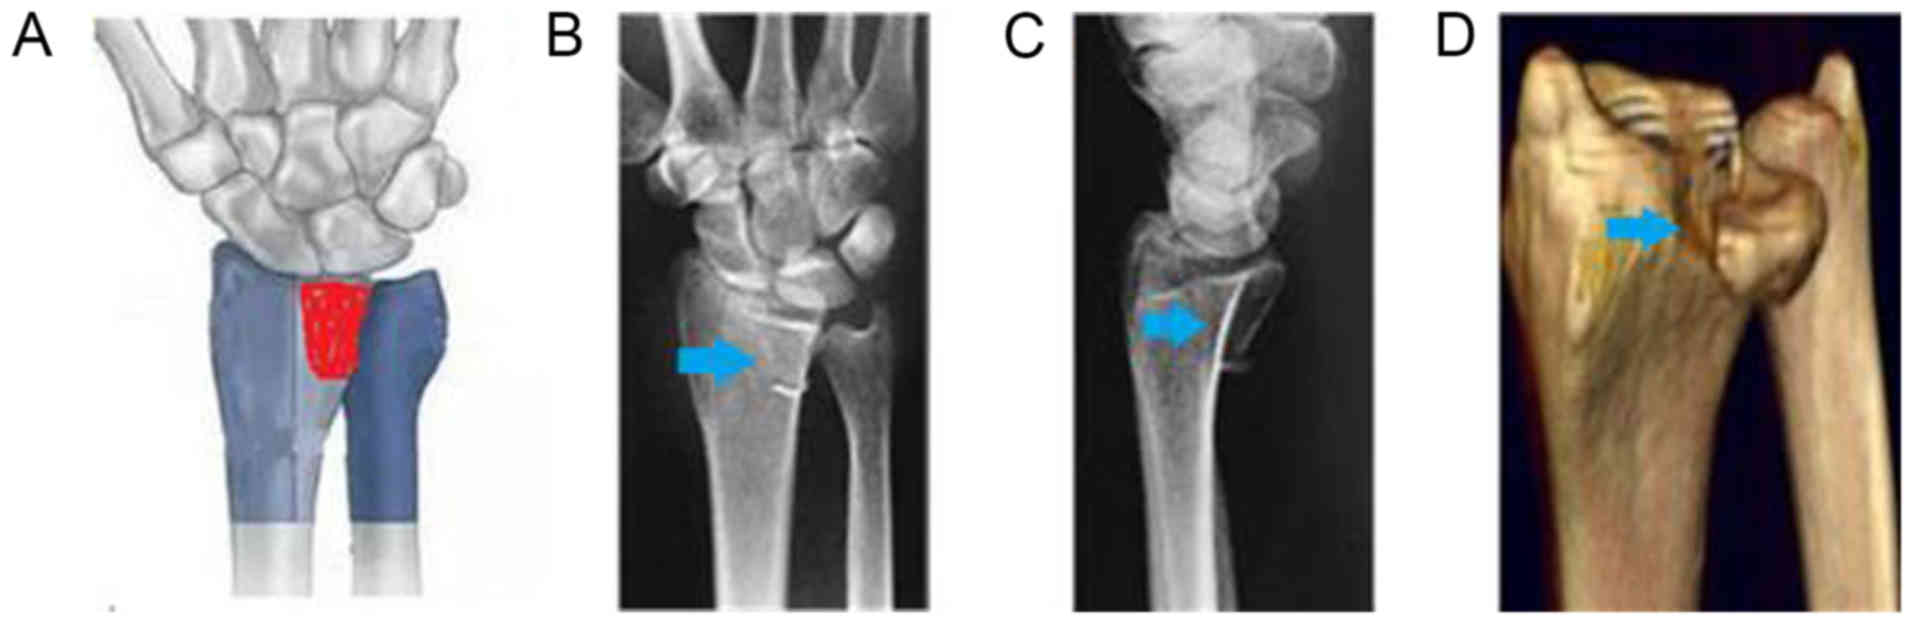

Due to differences in the extent and complexity of force at the time of injury, wrist position and bone condition, die-punch fractures may not only affect the ulnar demifacet of the distal radius but also the radial demifacet of the distal radius. These fractures include articular surface collapsed fractures and articular surface split fractures, as well as marginal fractures on the volar or dorsal side (2). According to the ‘three-column theory’ of distal radius fractures proposed by Rikli and Regazzoni (7) (Fig. 1), the die-punch fractures may be classified into the following two types: Single column and double column (Figs. 2 and 3A). A die-punch fracture is a rare occurrence. The Müller-AO classification of distal radius fractures includes die-punch fractures, although no specific system currently exists for the classification of die-punch fractures. Although certain studies have described a classification system for single-column die-punch fractures of the distal radius (2,8), the classification of double-column die-punch fractures remains to be established.

Figure 1.

Illustration of the three-column theory of distal radius fractures.

Single-column die-punch fracture. (A) Sketch of a single column die-punch fracture (red area indicates fracture site). (B) Anteroposterior and (C) lateral radiographs. (D) CT image. Arrows indicate the fracture site.